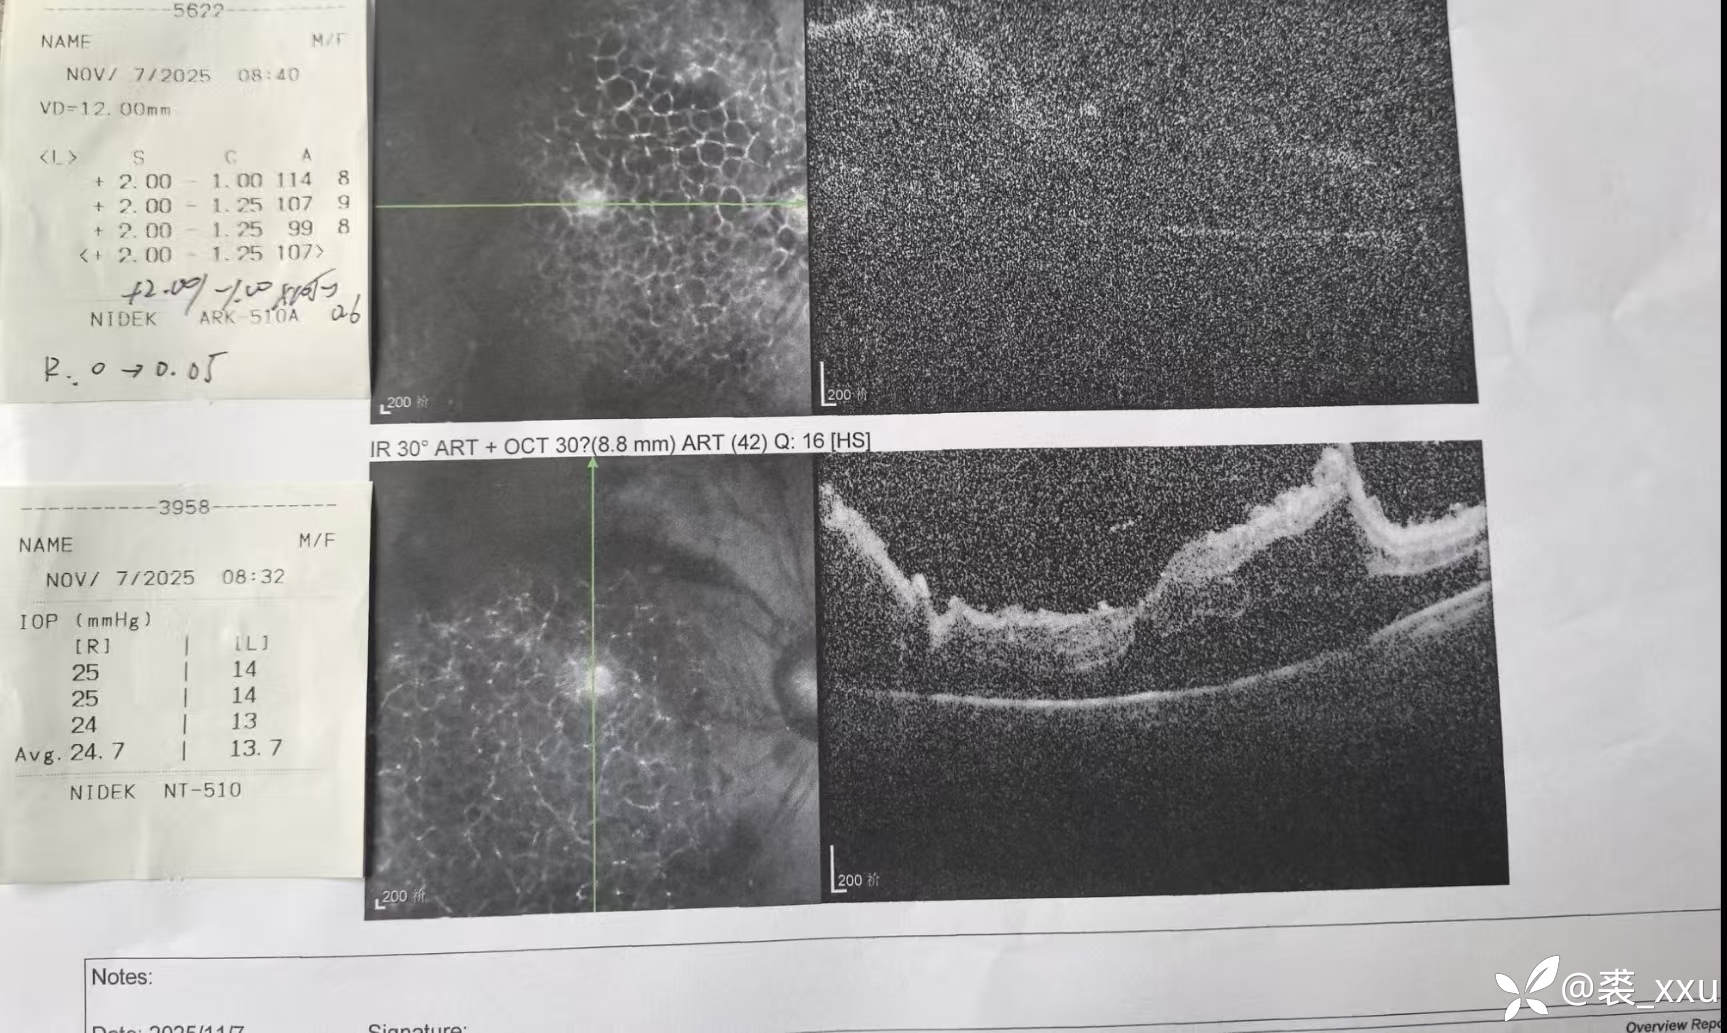

糖网6期,已出现牵拉裂孔,糖网牵拉裂孔一般不会和常规网脱一样视网膜容易飘动,切膜困难,因为其下为粘稠的网膜下液,但如出现医源性裂孔进入灌注液切膜剥膜将会很困难。所以该病例做的比较保守,切膜不彻底,部分残留。

原牵拉裂孔处反复气交后打上激光和粘弹剂后重新放入灌注液。

这种牵拉裂孔脱离的患者不打气打油安全吗?